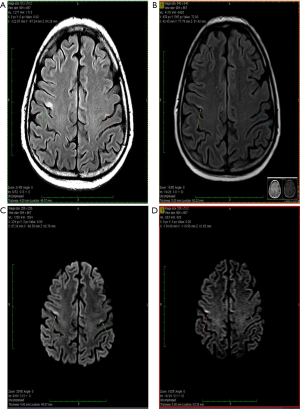

About one year after the allo-SCT, in July 2019, the patient presented in emergency with an episode of generalized seizures. He also associated dyspnea, sore throat and some involuntary movements of the left side of the face, but no adenomegaly or hepatosplenomegaly. The CT-scan was normal, and the CSF fluid was clean. Immunology assays and CSF virology tests for VZV, HHV-1, HHV-2, CMV and BKV were all negative, possible differential diagnoses remaining blinatumomab neurotoxicity and CNS relapse (262). A brain MRI was performed showing several millimetric demyelinating lesions scattered through the white matter, but also one bigger lesion in each precentral gyrus. The one in right precentral gyrus had 18/6 millimeters and his exact position was the superior facial area of the motor homunculus, possibly explaining the left facial involuntary movements. Both emit high signal in T2-weighted scan and are also seen in FLAIR scan, suggesting irreversible ischemic lesions. The MRI images are found in Figure 1. The patient state got worse, even with steroid and antiepileptic therapy, and a PET-CT performed in Vienna certified the diagnosis of isolated CNS relapse with extensive lesions. The positron emission tomography (PET-CT) images are found in Figure 2. He died soon thereafter, in September 2019.